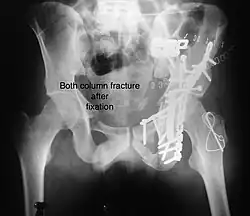

Both column fracture showing floating weight bearing dome

Both column fracture after fixation with screws and plates

Combined both column fractures | These are the most complex injuries. Here the weight bearing roof or dome of the acetabulum is a floating piece. This adds to complexity of management.

All three x-ray views plus CT scan is a must for diagnosis and management of this complex injury.

Like any other acetabular fracture, if the femoral head is dislocated out of the socket, early reduction into socket is a priority. However, in this injury, non-operative treatment rarely gives satisfactory results. Surgical management is ideal. The choice of approach rests with the surgeon, but going from front, or anterior approach is must. The posterior injury may be tacked with anterior approach by experienced surgeon. If the patient is unfit to undergo major surgery due to any reason, longitudinal traction to achieve secondary congruence of hip may help to restore hip function, though partially. |